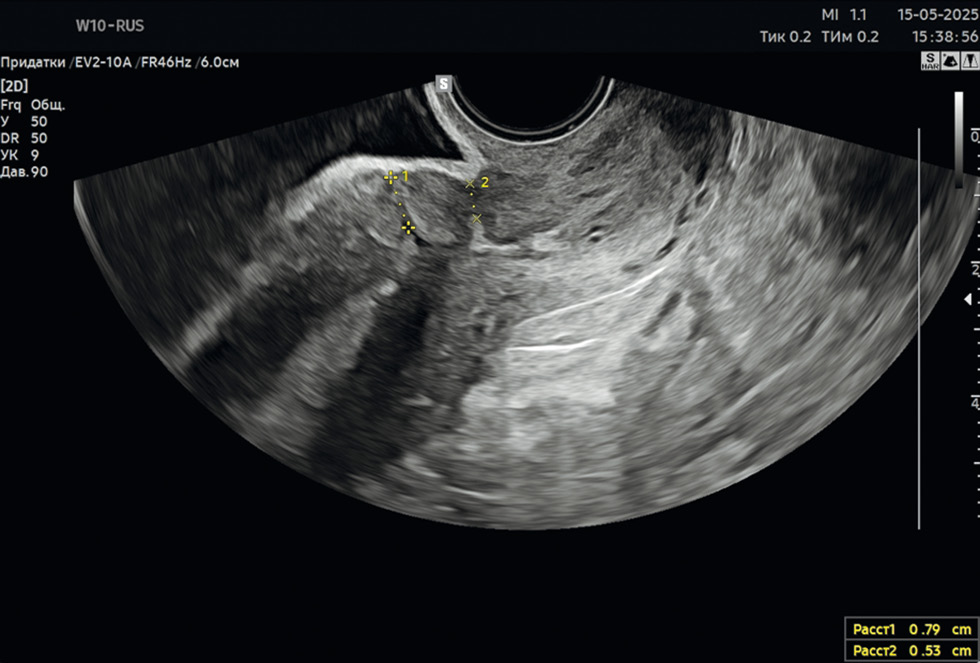

- Изменения в структуре брюшины и контурах органов: локальное утолщение париетальной брюшины и/или контура смежных органов, сопровождающееся повышением эхогенности (рис. 1, 2).

Рис. 1. Спаечный процесс в малом тазу. 2 мес. после операции кесарева сечения. Деформация стенки мочевого пузыря.

Fig. 1. Pelvic adhesions. 2 months after a caesarean section. Bladder wall deformation.

Кроме того, признаками спаечного процесса могут быть деформация стенок мочевого пузыря, формирование ниши в области послеоперационного рубца.